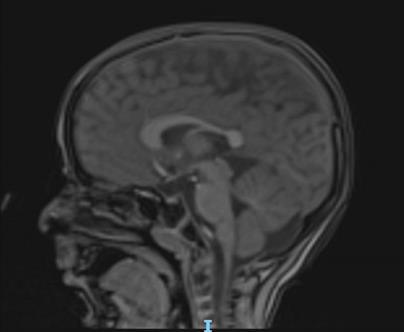

Хірургія SDR - 17/02/2022 o